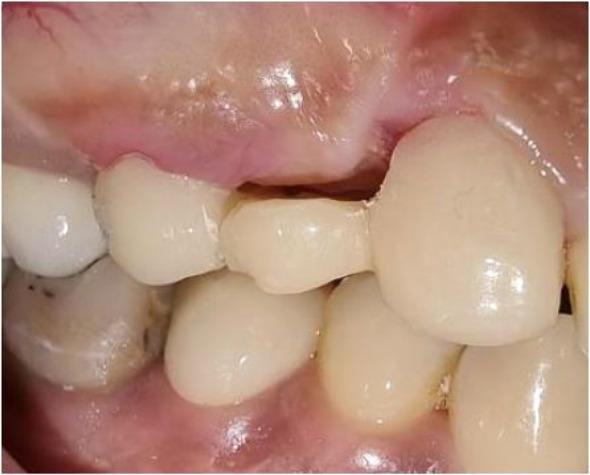

Peri-implantitis leads to gradual peri-implant bone loss. Severe and extreme cases lead to complete implant failure and imply lost implants have to be removed. Residual ridge deformity management after implant removal is one of the factors contributing to improved aesthetic and functional results. Various grafting procedures have been developed to achieve this goal. This report describes a case of implant removal from the upper right first premolar due to advanced peri-implantitis in a 51-year-old female patient. Guided bone regeneration with a alloplastic bone graft and resorbable collagen membrane combined with roll pedicle connective tissue graftt was used for both socket and soft-tissue augmentation. This was combined with ovate design conventional provisional bridge. After a 6-month of healing phase, a perfect adaptation of the marginal gingiva around the provisional restoration was obtained. Cone beam computed tomography revealed significant bone fill and buccolingual dimensional stability. A conventional all-ceramic bridge with an oval pontic design was chosen as a definitive prosthetic solution to compensate for edentulism and maintain the good aesthetic results. According to the encouraging result obtained in this clinical case, the conventional prosthetic restoration associated with surgical reconstruction of failing tissues can be considered as a successful treatment in the case of advanced peri-implantitis requiring implant removal.

种植体周围炎会导致种植体周围骨质逐渐流失。严重和极端的病例会导致种植体完全失败,意味着必须移除丢失的种植体。种植体移除后对剩余牙槽嵴畸形的处理是改善美学和功能效果的因素之一。已经开发了各种植骨手术来实现这一目标。本报告描述了一名51岁女性患者因严重种植体周围炎而拔除右上第一前磨牙种植体的病例。采用异体骨移植和可吸收胶原膜引导骨再生,并结合带蒂结缔组织瓣移植进行牙槽窝和软组织增量。这与卵形设计的传统临时桥体相结合。经过6个月的愈合期,临时修复体周围的边缘牙龈实现了完美贴合。锥形束计算机断层扫描显示骨填充显著且颊舌向尺寸稳定。选择了具有椭圆形桥体设计的传统全瓷桥作为最终修复方案,以弥补牙列缺失并保持良好的美学效果。根据该临床病例获得的令人鼓舞的结果,对于需要移除种植体的晚期种植体周围炎病例,与失败组织的手术重建相关的传统修复体可以被视为一种成功的治疗方法。